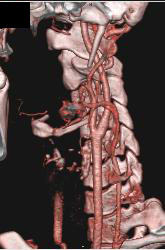

Normal Carotid Artery